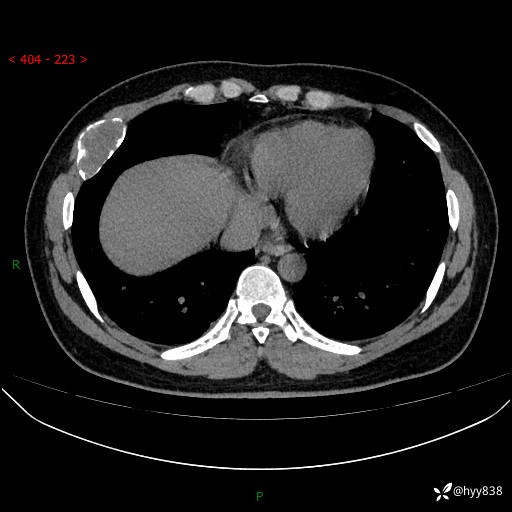

胸部CT平扫